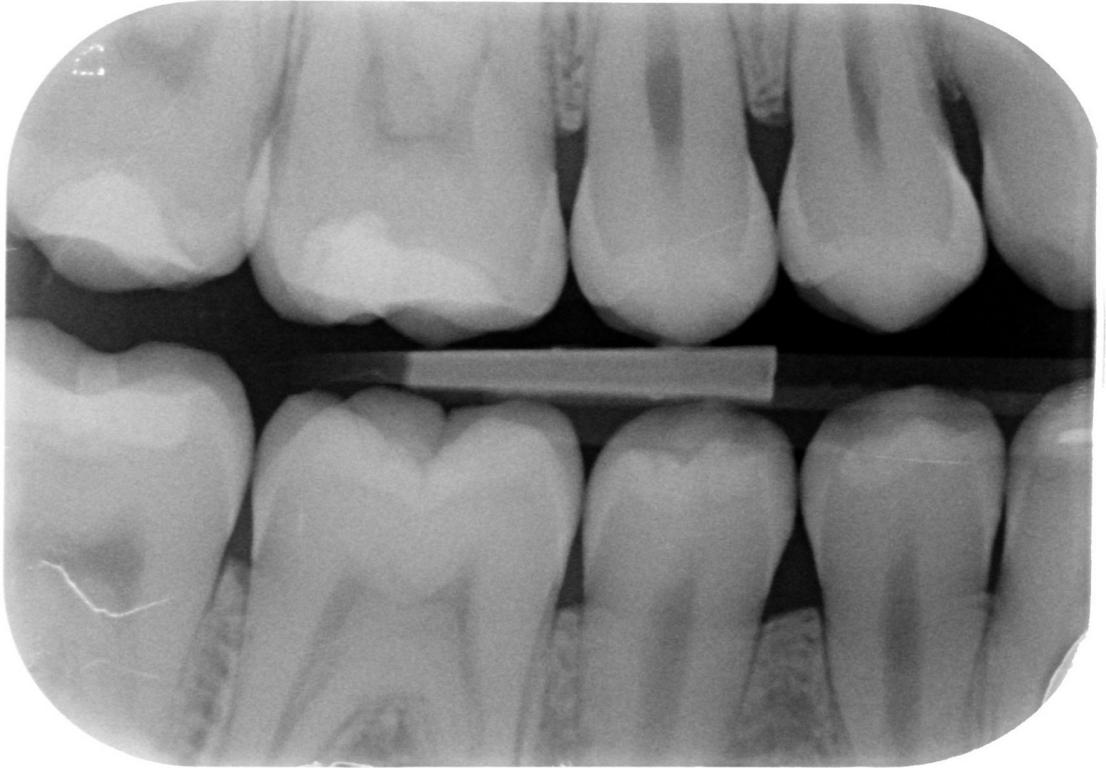

Röntgenfoto’s zijn van groot belang voor tandheelkundige diagnostiek. Tegelijkertijd brengt het gebruik van straling mogelijke gezondheidsrisico’s met zich mee. Daarom is het essentieel dat alle leden van het tandheelkundig team die met röntgenopnamen werken, beschikken over basiskennis van straling en weten hoe ze zich kunnen beschermen tegen schadelijke effecten. Deze e-learning biedt de noodzakelijke achtergrondkennis over de eigenschappen van straling, stralingsrisico’s en beschermingsmaatregelen. Zo kun je bijdragen aan een veilige en verantwoorde toepassing van röntgendiagnostiek, waarbij de voordelen voor de patiënt altijd opwegen tegen de risico’s. Hoewel de tandarts verantwoordelijk is voor het indiceren van röntgenopnamen, mogen andere teamleden de belichting uitvoeren — mits dit gebeurt onder toezicht én zij beschikken over de wettelijk vereiste röntgenopleiding. Deze nascholing ondersteunt jou in het opdoen van die kennis en is bedoeld als voorbereiding of aanvulling op de verplichte röntgencursus.